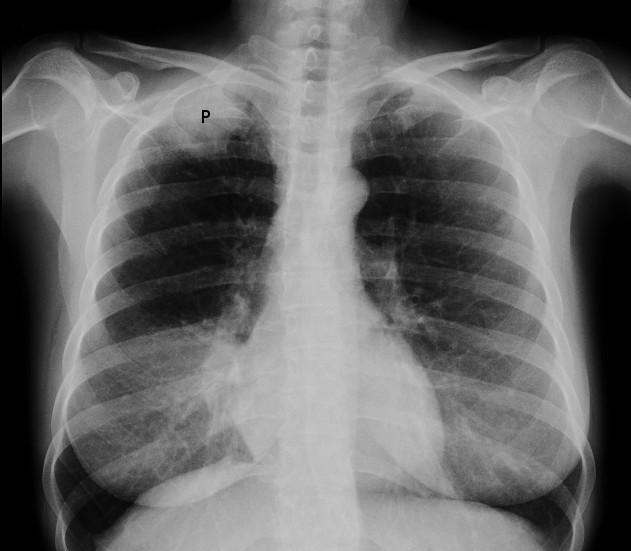

Radiographie de la tumeur de Pancoast

© Jmarchn (Own work), CC BY-SA 3.0, via Wikimedia Commons

Par Jmarchn, CC BY-SA 3.0via Wikimedia Commons